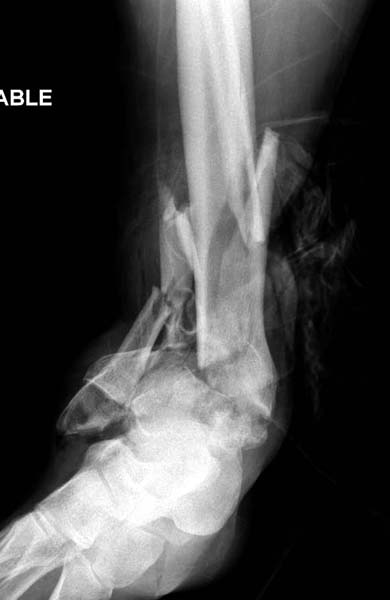

Современную тактику лечения переломов пилона описали коллеги, а мне остается подтвердить клинически. В многоэтапном лечении главное - это предупреждение сокращения мягких тканей, от которого зависит судьба конечности. Дистракция любым наружным фиксатором, и по готовности мягких тканей - премежуточная или окончательная фиксация.

В нашем случае, травма в результате коллапса крыши. Открытый перелом. Ургентные Irrigation and Debridment, дистракция наружным фиксатором. В госпиталях первого уровня редко бывает изолированная травма, и на другой стороне повреждение стопы с переломом навикулярной кости. После обработки раны - вакуум и двухсторонние наружные фиксаторы.

Вначале нет смысла заказывает КТ, только дистракция организует на свое место свободных фрагментов. По топографии отломком преоперационный план, а готовность мягкой ткани подтвердит появившиеся морщины на поверхности кожи, “Wrinkle Sign”.